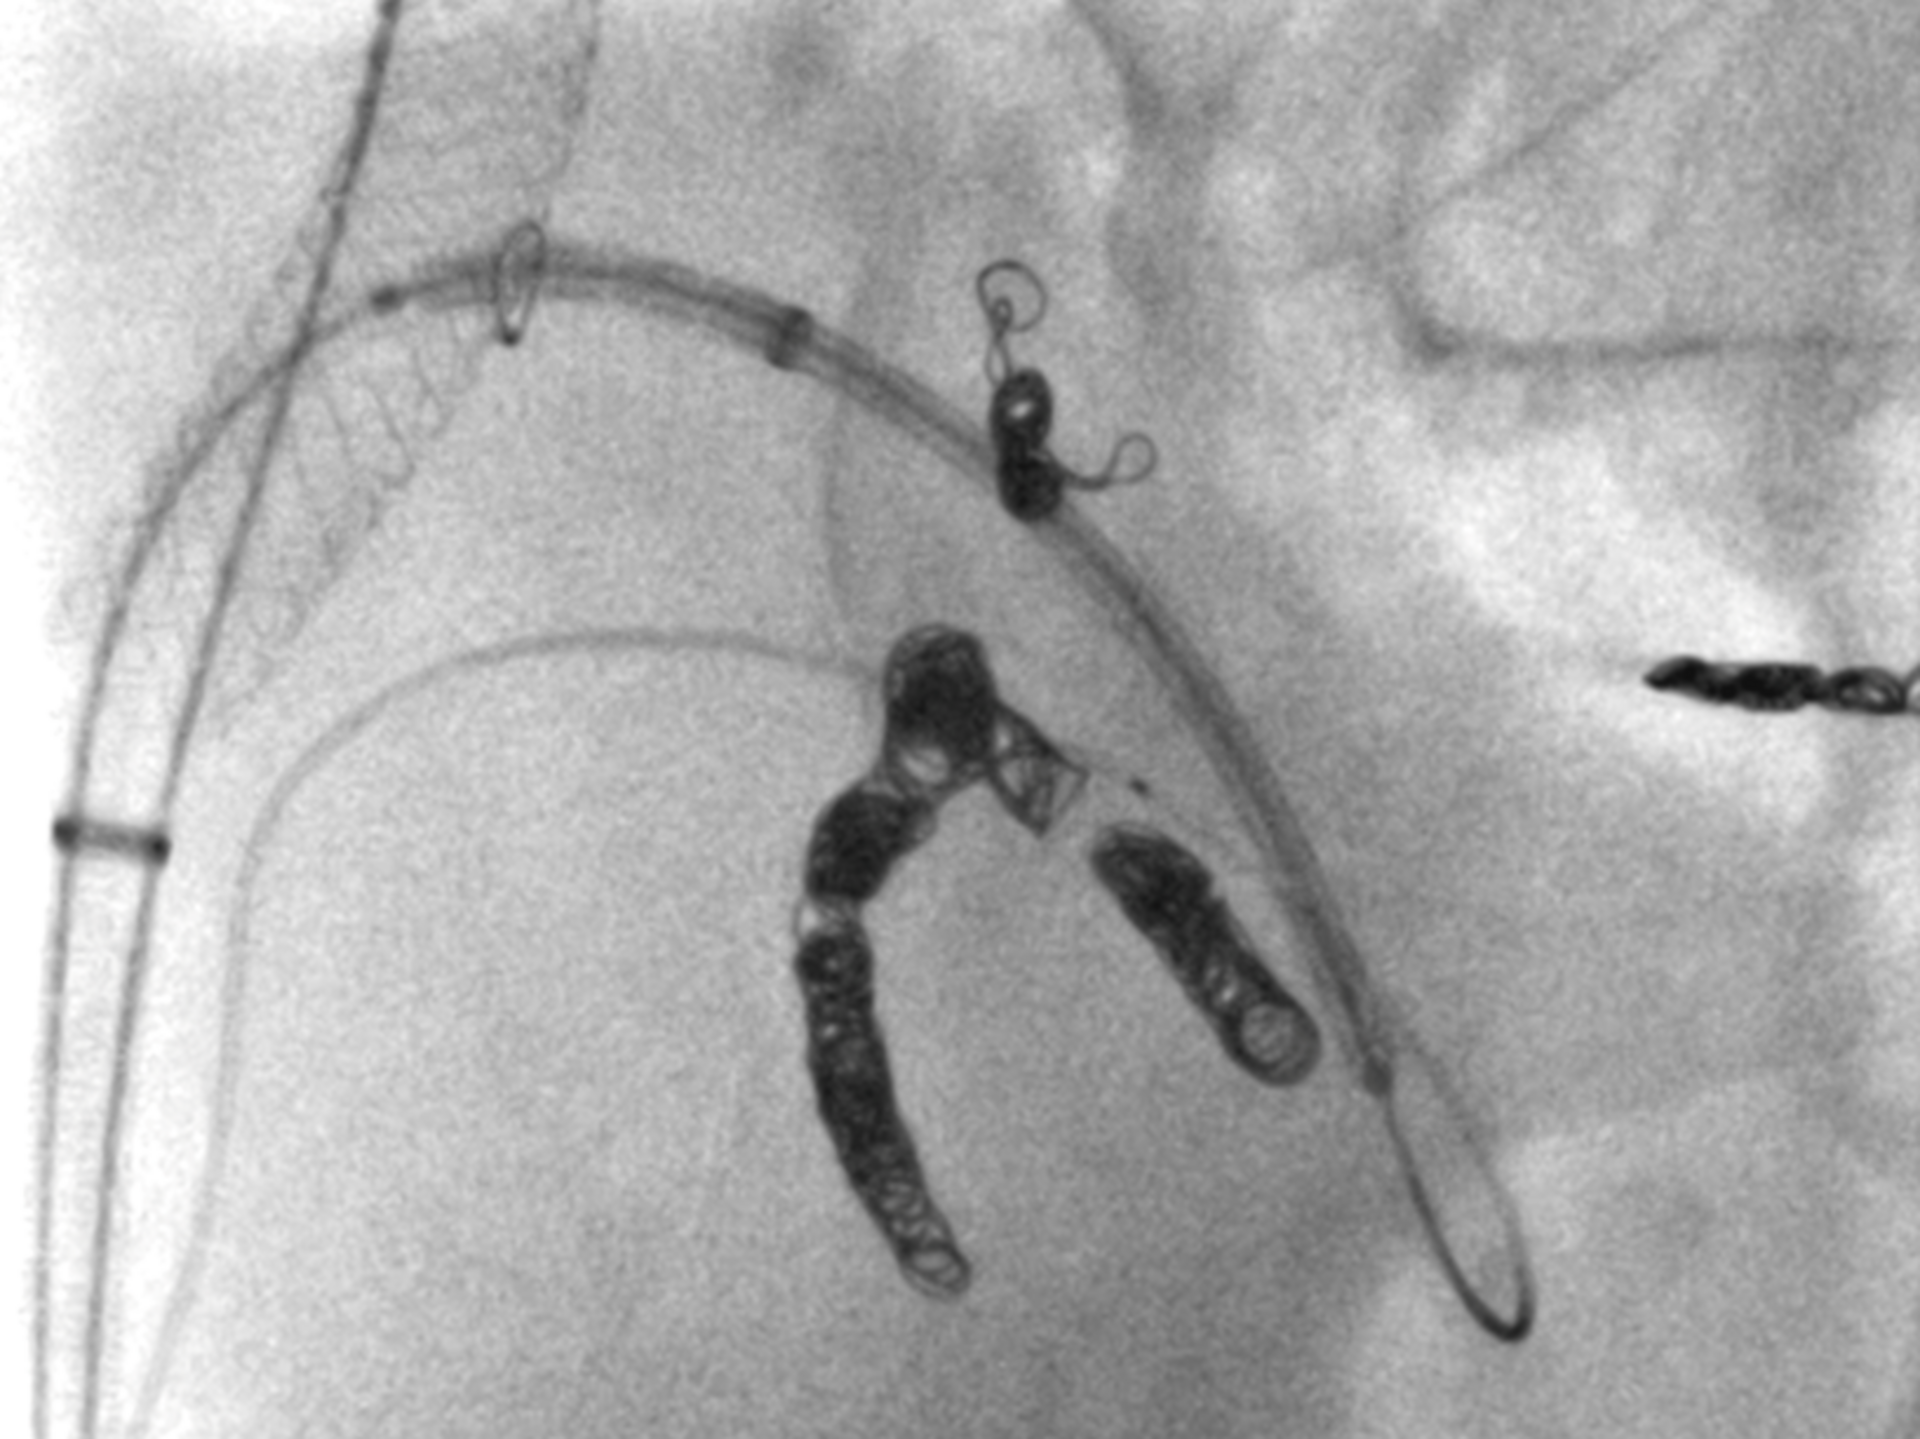

Abhängig von Ausdehnung und Lokalisation des Aneurysmas ist die endovaskuläre Therapie eine minimalinvasive, für die Patient:innen sehr schonende Behandlungsoption. Nach örtlicher Betäubung und gegebenenfalls leichten angstlösenden bzw. beruhigenden Medikamenten führen die Expert:innen der Abteilung für Radiologie und Nuklearmedizin durch die Haut eine übliche Punktion der Leistenarterie als Zugang zum Gefäßsystem durch. Anschließend wird mit Hilfe bildgebender Verfahren über ein Kathetersystem eine ummantelte Gefäßstütze (Aorten-Stentgraft) präzise innerhalb des erkrankten Gefäßabschnittes eingesetzt, um die Gefäßaussackung von innen abzudichten.

Bei einem nicht unerheblichen Anteil der Betroffenen sind keine Standard-Stentgraft-Materialien verwendbar, um eine sichere Abdichtung zu gewährleisten. In diesen Fällen kommen maßgefertigte Stentgraft-Prothesen zum Einsatz. Diese haben abhängig von der Lokalisation Verbindungen zu den übrigen wichtigen Baucharterien wie Nieren und Darm.

Ist die Gefahr eines Aortenrisses sehr hoch, beispielsweise aufgrund eines sehr großen Aneurysmas oder Schmerzsymptomatik durch das Aneurysma, kann die Fertigungszeit der individuell produzierten Aortenstentgrafts von mehreren Wochen nicht abgewartet werden. Alternativ kommen hybride endovaskuläre Techniken zu Einsatz, die Standardmaterialien miteinander kombinieren, um eine umgehende zeitnahe Versorgung durchführen zu können.

Entsprechend unserem Anliegen, so viel wie möglich an vorhandenen Gefäßen zu erhalten, gelingt auch der Erhalt der Beckenarterien bei ausgedehnten aorto-iliakalen Aneurysmen mit diesen Techniken. Diese Gefäßversorgung bildet einen wichtigen Umgehungskreislauf bei arterieller Verschlusskrankheit zum Bein oder vaskulär bedingter erektiler Dysfunktion.